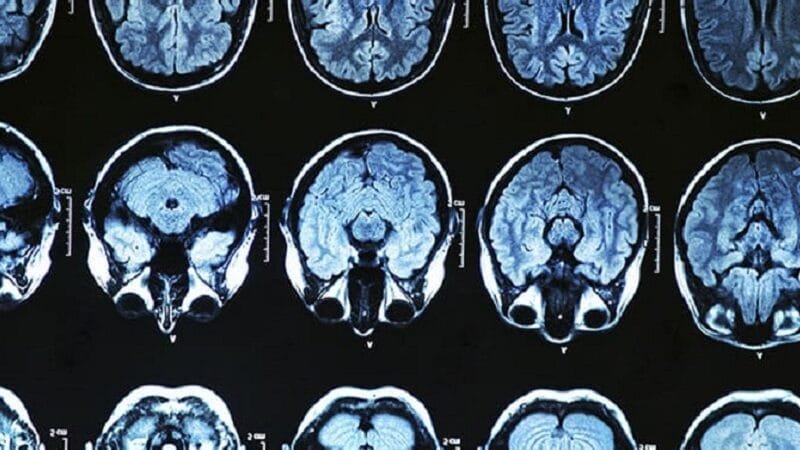

O medicamento atua se ligando aos amiloides, reduzindo a formação de placas da proteína anormal no cérebro de pacientes